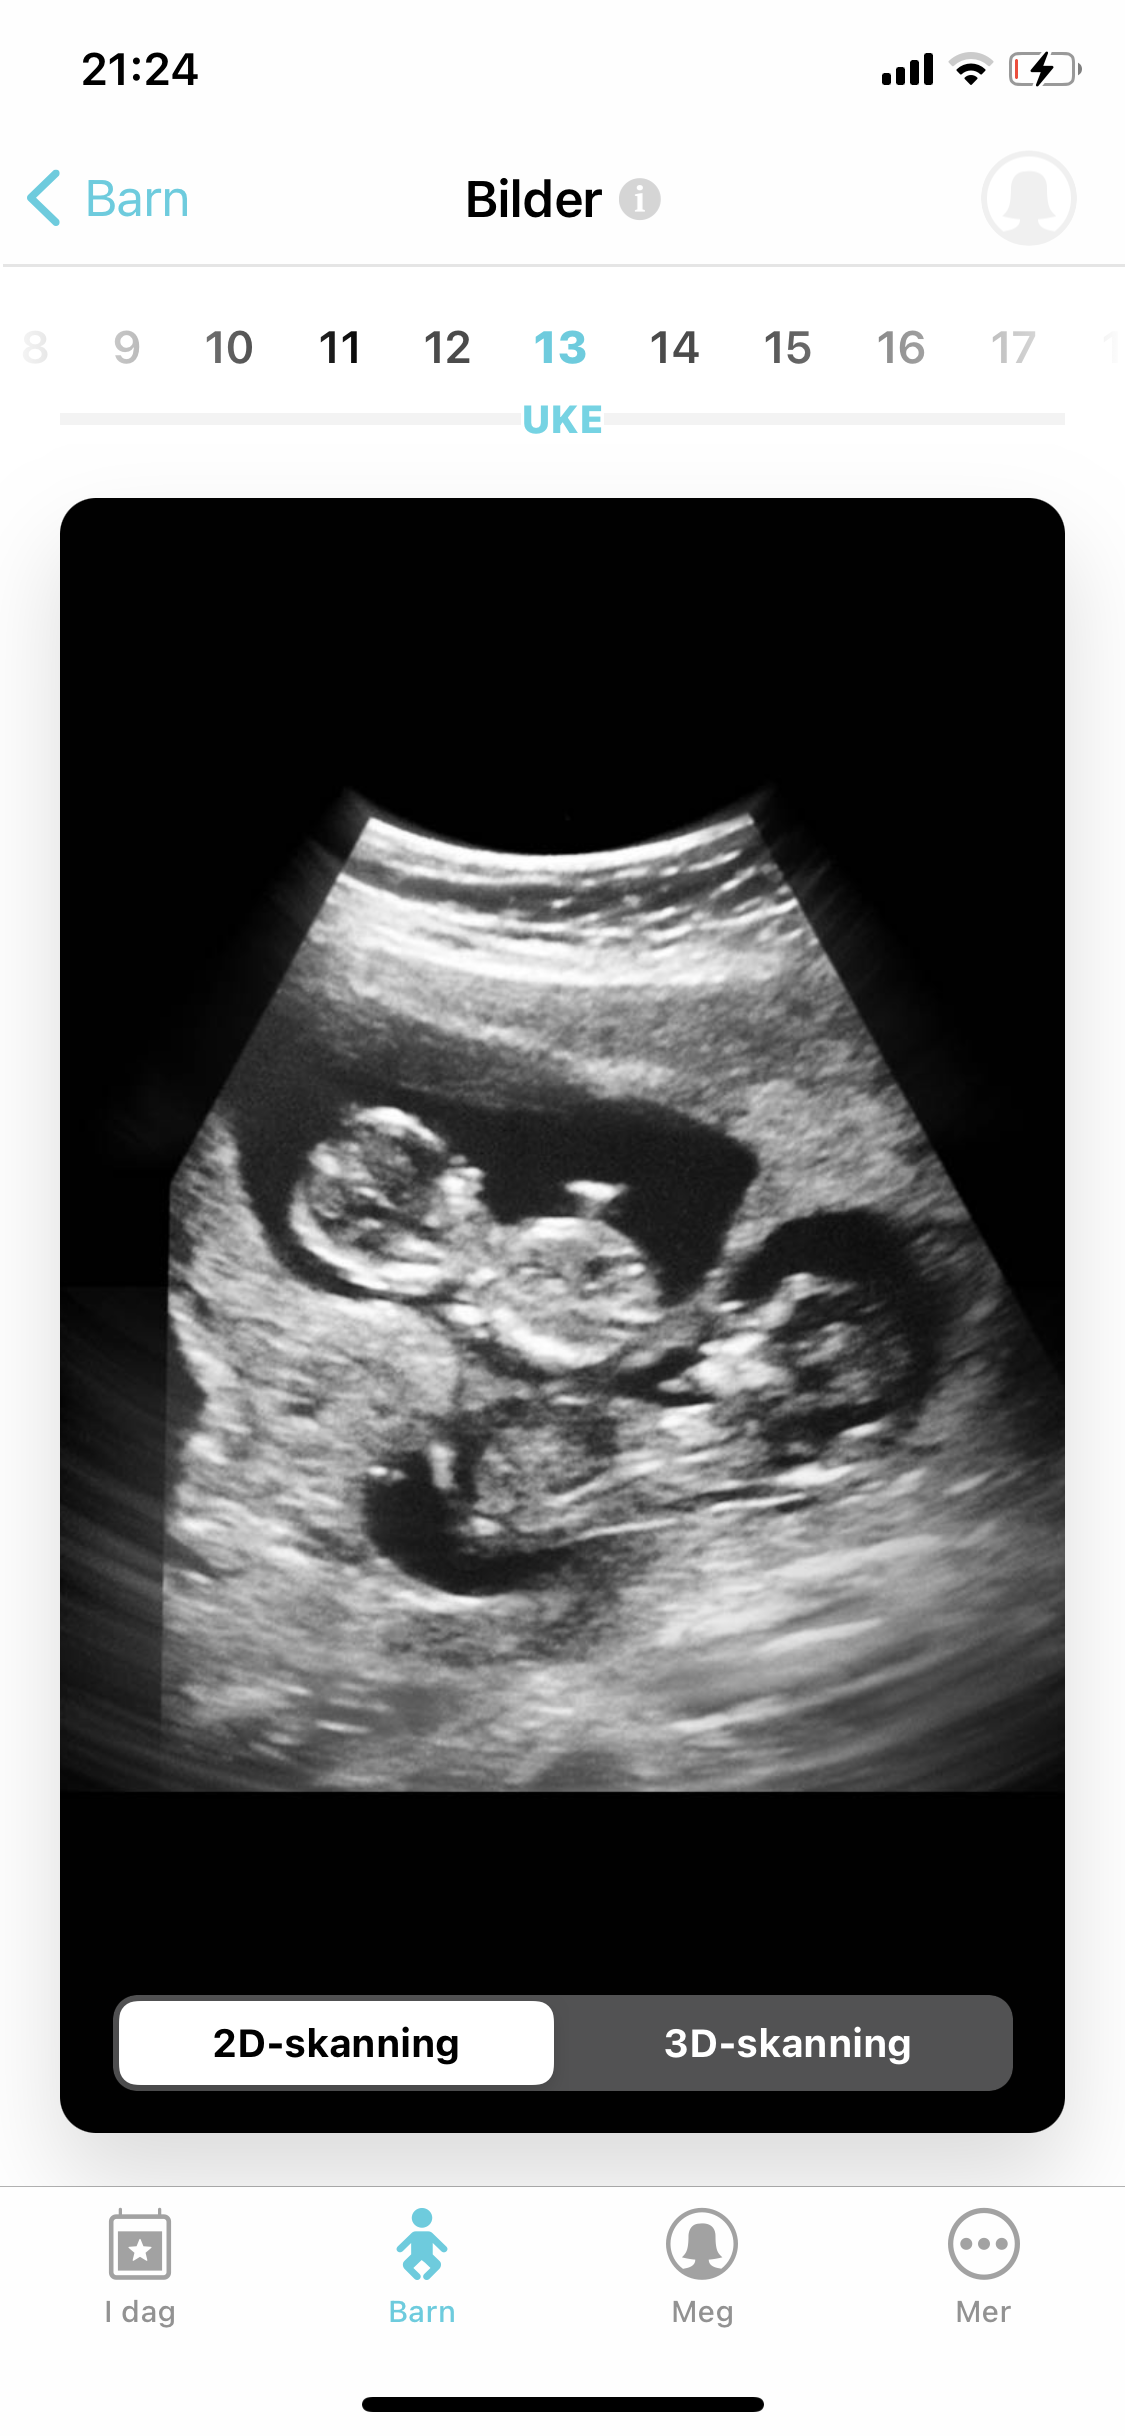

AnonymBruker Skrevet 2. januar 2021 #1 Skrevet 2. januar 2021 Hva kan man se på ultralyd i uke 13? Anonymkode: 8b43b...969

AnonymBruker Skrevet 2. januar 2021 #2 Skrevet 2. januar 2021 Man ser et foster som ser ut som en liten,rar baby Her står det mer om hva man kan se de ulike ukene https://www.jordmorklinikken.no/tjenester/ultralyd/ultralyd-uke-for-uke/ Det er ikke mulig å fastslå kjønn så tidlig, selv om noen prøver å gjette Anonymkode: 30a78...d8d

AnonymBruker Skrevet 2. januar 2021 #3 Skrevet 2. januar 2021 Spørst hva du mener, men ser en del. jeg personlig så ryggrad, hjerne , hjertekammer etc. JM så Jonas klrt dette +kjønn. man ser også fingre Anonymkode: 4422c...3a7

Kenelz Skrevet 2. januar 2021 #4 Skrevet 2. januar 2021 Skjønte ikke så mye, syntes det såg ut som en mennskelig reke uansett hvor mye legen pekte på hjertet, hjernen, osv. 😂

AnonymBruker Skrevet 2. januar 2021 #6 Skrevet 2. januar 2021 Det kommer an på hvem du går til. Nakkefolden er aller best å måle i uke 10-14. På OU ser man den stort sett ikke. Kjønn er også mulig å se hos de som virkelig kan slikt. Han jeg har vært hos tre ganger gjør en såkalt kvalifisert gjetning, og kan med 90% sikkerhet si hvilket kjønn det er. Anonymkode: d019d...b9f